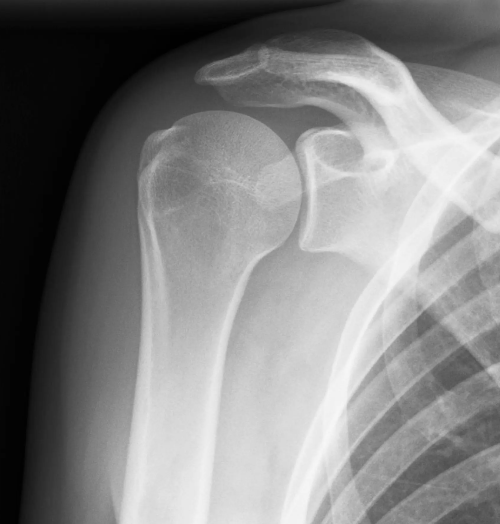

The shoulder is a ball and socket joint. It consists of a round head of the upper arm bone called the humeral head. This ball fits into a socket in the shoulder called the glenoid fossa. A total shoulder replacement removes the damaged round head and socket and replaces them with metal and plastic parts, while maintaining their anatomical position.

A partial shoulder replacement involving the replacement of only the ball or the humeral head with a metal ball and stem. This surgery may be recommended when the humeral head is severely damaged but the socket or the glenoid fossa is normal.

A partial shoulder replacement involving the replacement of only the surface of the ball or the humeral head with an artificial cap without the stem. This is an alternative to the stemmed hemiarthroplasty allowing for more bone preservation.